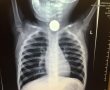

במאה שערים: תינוק נולד ללא דופק; מצבו קשה

לאחר החייאה ממושכת שב הדופק • התינוק פונה לבית החולים במצב קשה מאוד